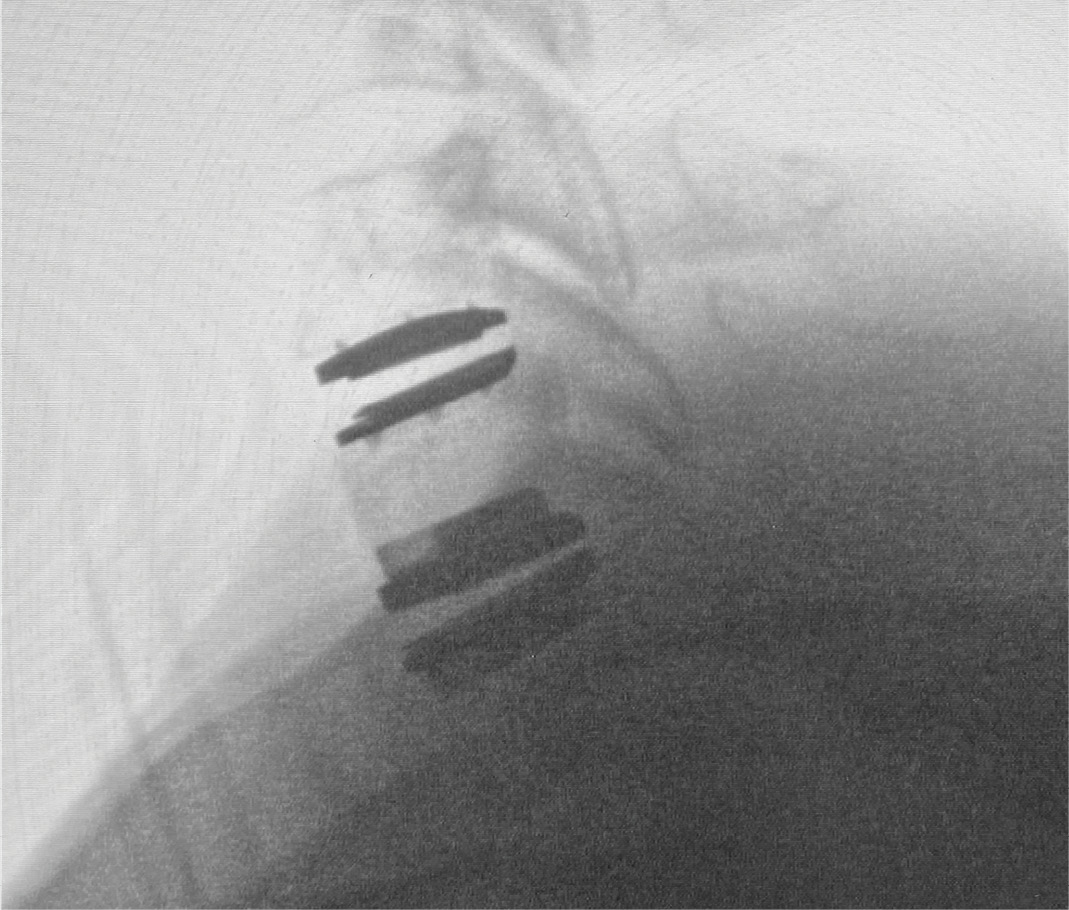

During intra-operative trialing after discectomy and foraminotomies, I felt that the best fit at the C6-7 level was with a prodisc C SK—6mm tall by 18mm deep (Figure 6a). I then performed the discectomy and trialing at the C5-6 level and felt that the prodisc C Vivo was a perfect fit here (Figure 6b).